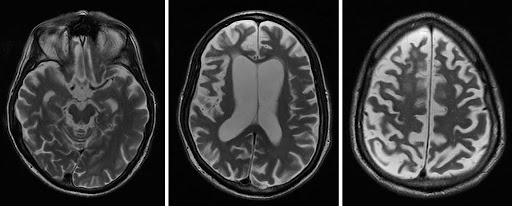

CBD diagnosis is primarily based on a detailed neurological exam and review of symptoms. Brain imaging such as MRI can rule out other causes, and functional scans like FDG-PET may reveal patterns of reduced brain metabolism characteristic of CBD.